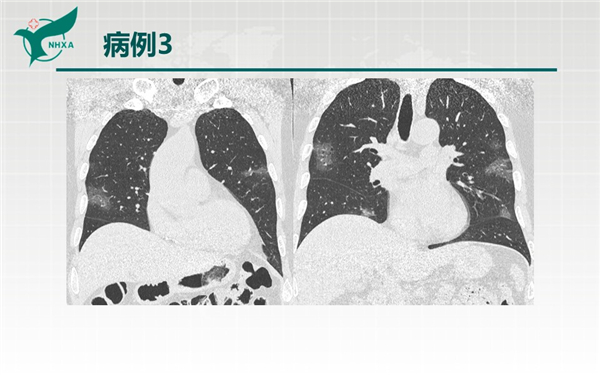

【病例分享】新型冠狀病毒肺炎3例(西安市第九醫(yī)院)

幻燈片10.jpg